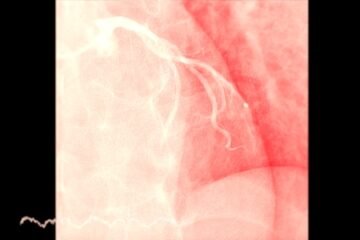

Von Hipela–Lindau slimība nereti izraisa daudz jautājumu un spēcīgas emocijas, tostarp trauksmi, bailes un nenoteiktības sajūtu. Šī iedzimtā slimība ir saistīta ar cistu un audzēju veidošanos dažādās organisma vietās, visbiežāk galvas smadzenēs, mugurkaula kanālā, aizkuņģa dziedzerī, tīklenē, nierēs vai virsnierēs.